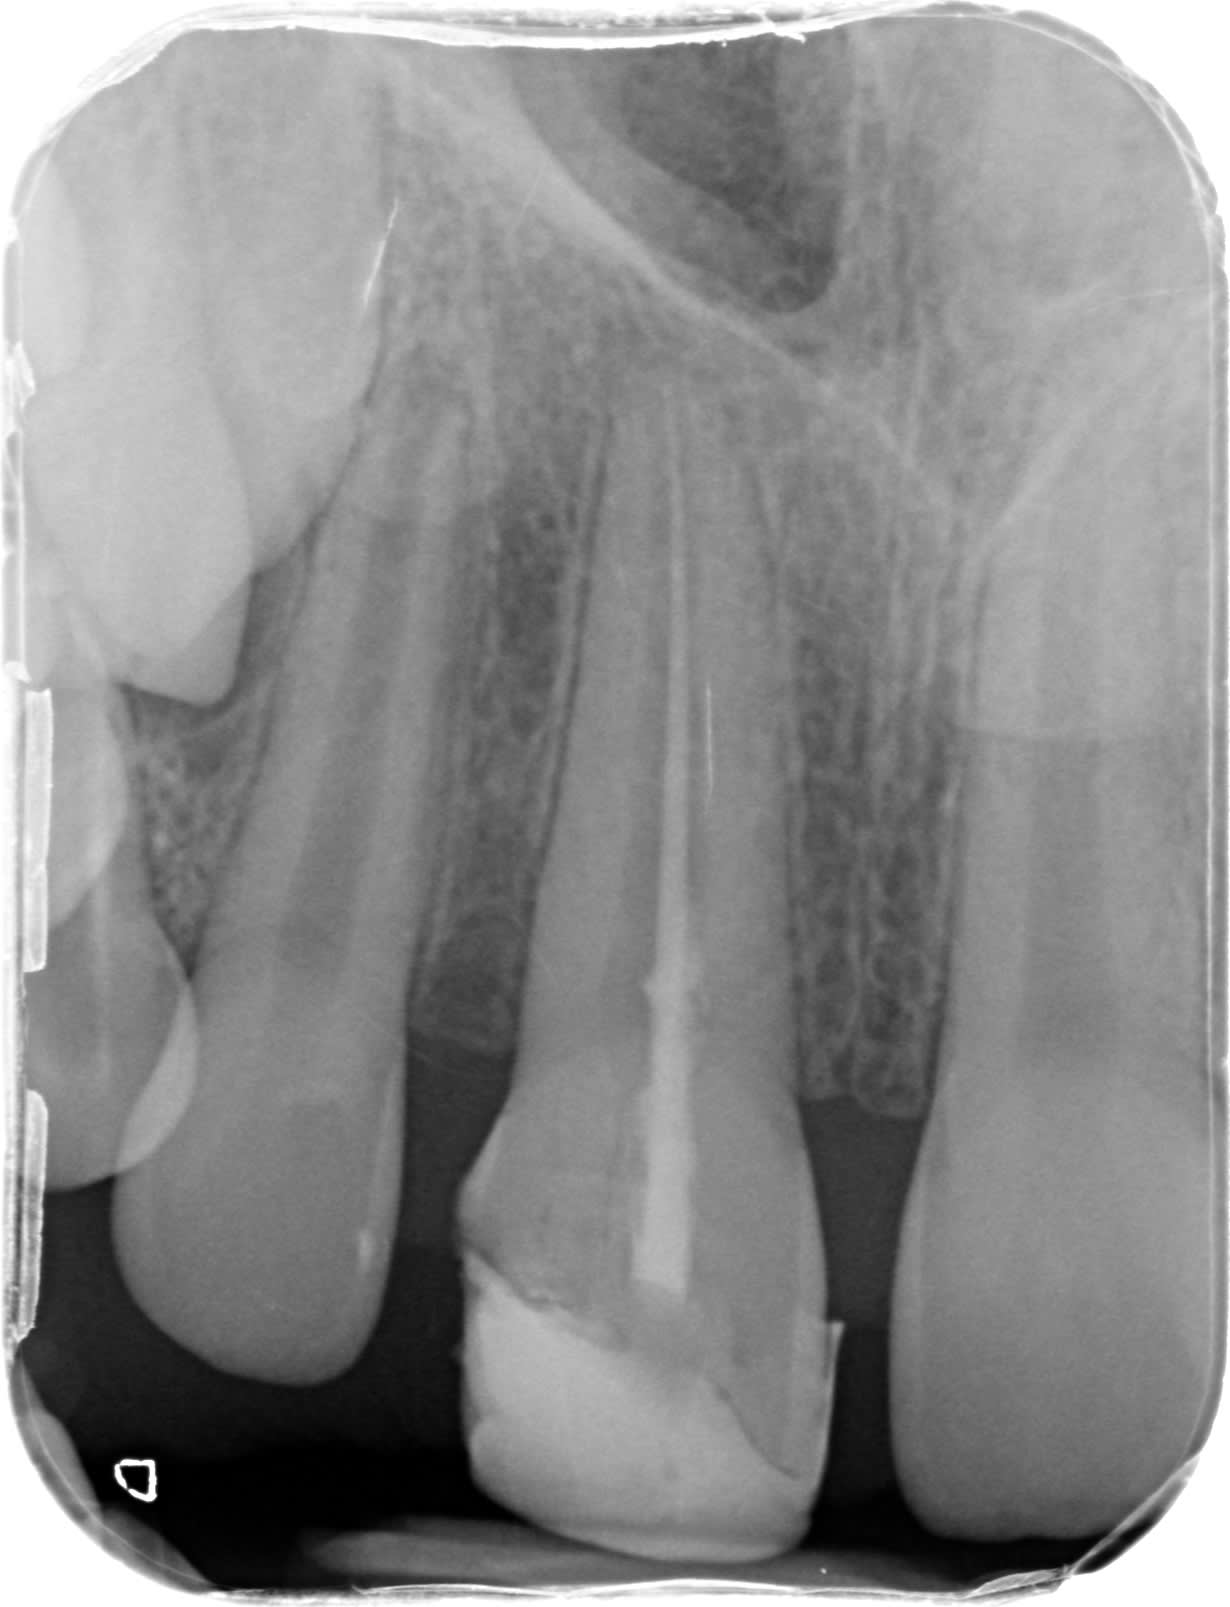

Poser un pangen et coter un comblement c'est du vol. Selon mon CD conseil coter une photo pour justifier ton acte et ou enregistrer tes rapports occlusaux est justifié. bien sur si tu fais un compo de merde dans la salive prendre une photo NR c'est du vol. je pense pas voler mes patients. Les parents du gosse dont je joint le cas n'ont trouvé que je suis un voleur ( malgré les 400 NR) alors qu'ils attaquent le confrère au tarif conventionné.

Difficile a voir sur la radio ; tu as mis un pivot?,

5inon, je pense qu'ils vont attaquer deux dentistes!

A ce stade une dent provisoire et zou!